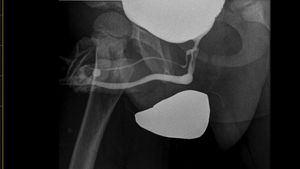

Cistouretrografía miccional: duplicación uretral tipo 2 coronal completa según la clasificación de Lima et al.1.

Presentamos el caso de un varón de 5 años remitido a consulta de urología pediátrica por presentar doble meato uretral, asintomático: no presentaba micción ni goteo por el meato dorsal. En la exploración física se aprecian 2 meatos uretrales: uno normoposicionado y otro dorsal (fig. 1). Se solicita cistouretrografía miccional que confirma duplicidad uretral completa con uretra normal y uretra accesoria con origen en la uretra principal prostática, a nivel del veru montanum (fig. 2); se corresponde con duplicación uretral tipo 2 coronal completa según la clasificación de Lima et al.1. Se interviene quirúrgicamente realizando circuncisión, disección y sección de la uretra doble dorsal de 5cm de longitud con ligadura de la base (fig. 3). Se deja sonda vesical de 8Fr. El paciente evoluciona favorablemente en el postoperatorio inmediato, retirándose la sonda vesical y siendo dado de alta a las 24h de la intervención. Permanece asintomático en los seguimientos clínicos posteriores.